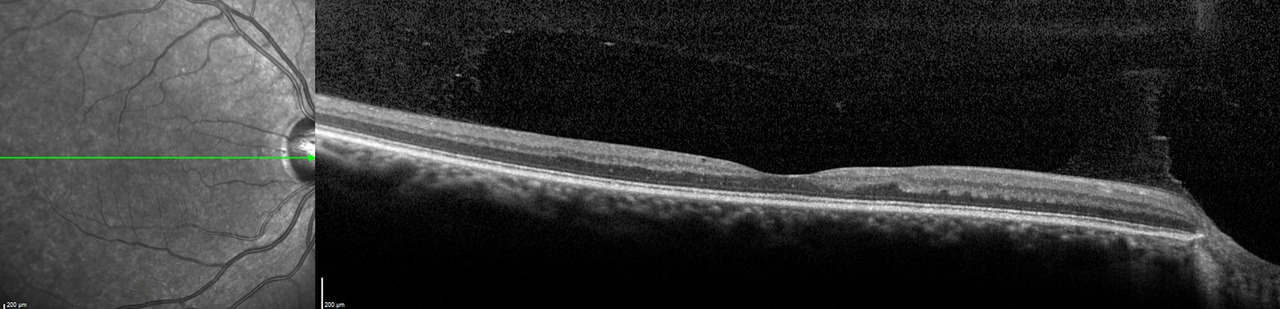

Voici les résultats de l’OCT maculaire :

Figure n° 1 (Source : Gabriel Hallali, centre hospitalier intercommunal de Créteil, service du Pr Souied, La Revue du Praticien)

L’OCT maculaire est normale. Il n’y a pas d’intérêt à ce stade à compléter les explorations avec une angiographie.

La présence d’une baisse d’acuité visuelle essentiellement de près et l’absence de cataracte ou d’anomalie maculaire doit faire orienter vers une atteinte située sur le nerf optique ou rétro-orbitaire.